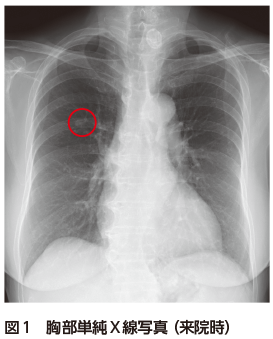

• A2:肺がんの可能性を考え,腫瘍マーカー,体幹部造影CT,可能であれば気管支鏡検査を行う.境界明瞭な結節影なので,肺クリプトコッカス症も鑑別に入れ,血清クリプトコッカス抗原の測定を考慮する.

胸部単純X線写真では右中肺野に右第7肋骨に重なって楕円形の結節影を認めた(図1).胸部CTでは右上葉S2の葉間胸膜直下に13 mmの境界明瞭な円形の結節を認めた.内部の濃度は不均一で,血管収束像や分葉状の辺縁は認めなかった(図2A,B).PET-CTでは同部位にSUVmax 12.56のFDG集積を認めた(図3).腫瘍マーカーは正常であった.CTでbronchus sign陽性の気管支は存在しなかったため,気管支鏡検査は施行せず,肺がんcT1bN0M0 StageⅠA2疑いとして診断・治療目的で右肺S2区域切除術を施行した.病理検査では多数の多核巨細胞を含む組織球が集簇した肉芽腫性の病変を認め,一部に変性壊死を起こしていた.Grocott染色で組織球に貪食される無数の酵母状真菌が観察され,肺クリプトコッカス症の診断となり,手術で病変は切除できているので無治療も選択肢だったが,患者と相談し,フルコナゾールの内服を開始した.

肺クリプトコッカス症はクリプトコッカス属真菌による感染症である.感染すると組織球が活性化して肉芽腫が形成され,真菌を封じ込める.CTでは肉芽腫形成を反映した結節を認める.同一肺葉内に多発する場合もあるが,本症例のような孤立性結節は,原発性肺がんとの鑑別が難しい.肺クリプトコッカス症のCT所見の特徴として,境界明瞭,胸膜直下が好発部位,空洞形成を伴うことがある,などがあげられる.しかし,spiculation,胸膜嵌入像,末梢血管の収束像,PET-CTでのFDG集積といった肺がんと酷似する所見を示すこともある1)